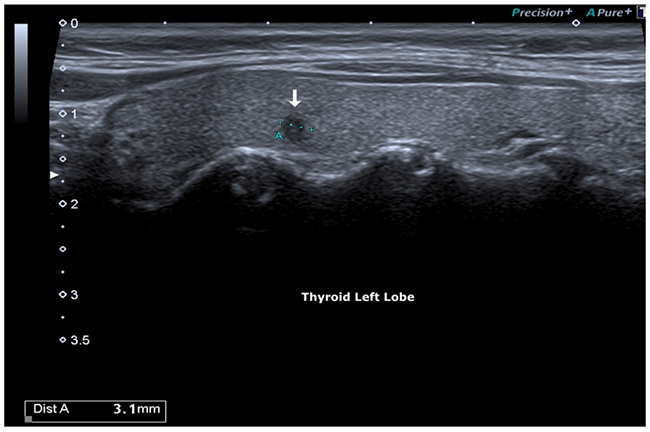

Bidimensional ultrasonography (DUS 2) using high frequency probes (13 - 15 MHz) (Toshiba Aplio 500) highlighted a highly suspicious micro-focus of the left lobe, of radial shape with markedly hypoechoic echostructure, irregular margins, size 0.3 cm (classified TI-RADS 5, very high risk lesion ATA guidelines).

Figure 1: Hypoecogenic micro-focus, irregular margins.

Figure 2: Micro-focus, irregular margins: 3 mm.

The micro-focus identified was localized at the middle third of the left lobe, presenting a radial shape, markedly hypoechoic echostructure, irregular margins, size 0.3 cm, characteristics with a high predictive for malignancy value (p <0.001) [19].